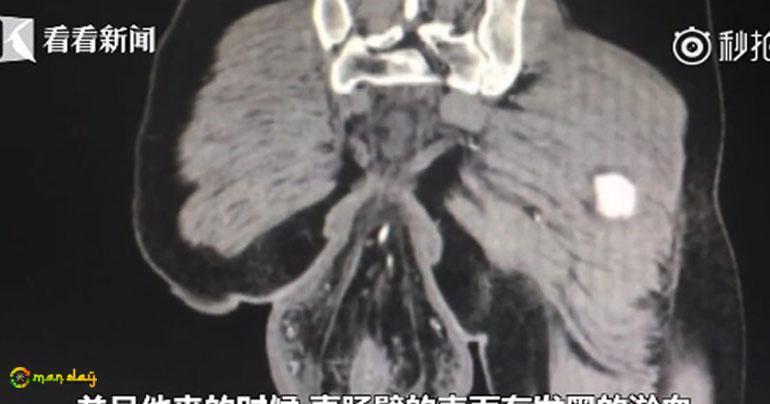

Images of a CT scan of the man's rear showed a big lump hanging outside his body.